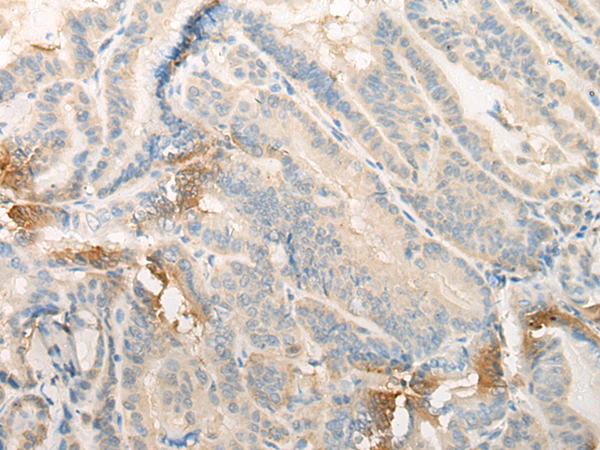

分类: 科研抗体货号: P06414别名:应用: IHC反应种属: Human